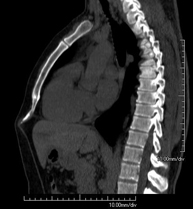

- Abdomen CT

Diagnostic test that involves obtaining high-definition anatomical images of the abdomen (liver, gallbladder, bile duct, pancreas, spleen, stomach, intestines, kidneys, vascular structures, bladder, uterus and ovaries, etc.) using CT (computed tomography) equipment. These images are then studied at a workstation capable of producing two-dimensional reconstructions in different spatial planes, and also 3D (volumetric) reconstructions. Most studies require the use of iodinated contrast to improve image definition.

- Abdominal and pelvic CT

Diagnostic test that consists of obtaining high-definition anatomical images (bone structures, vascular structures, liver, pancreas, gallbladder, kidneys, adrenal glands, spleen, small and large intestine, bladder, uterus and ovaries, prostate and seminal vesicles, ureters, etc.) using CT (computed tomography) equipment. Most studies require the use of iodinated contrast.

Prova diagnòstica que consisteix en obtenir imatges del tòrax d'alta definició anatòmica (pulmons, cor, mediastí, grans vasos, caixa toràcica, etc.) mitjançant l'ús d'un equip de TC (Tomografia Computeritzada). Aquestes imatges s'estudien posteriorment en una estació de treball que permet reconstruccions bidimensionals en diferents plans de l'espai i també reconstruccions tridimensionals (3D: volumètriques). Alguns estudis requereixen l'ús de contrast iodat per millorar la definició de les imatges. - TC Abdomen

Prova diagnòstica que consisteix en obtenir imatges de l'abdomen d'alta definició anatòmica (fetge, vesícula biliar, via biliar, pàncrees, melsa, estómac, intestins, ronyons, estructures vasculars, bufeta, úter i ovaris, etc.) mitjançant l'ús d'un equip de TC (Tomografia Computeritzada). Aquestes imatges s'estudien posteriorment en una estació de treball que permet reconstruccions bidimensional en diferents plans de l'espai, i també reconstruccions tridimensionals (3D: volumètriques). La majoria d'estudis requereixen l'ús de contrast iodat per millorar la definició de les imatges. - Lower leg rotational study using CT